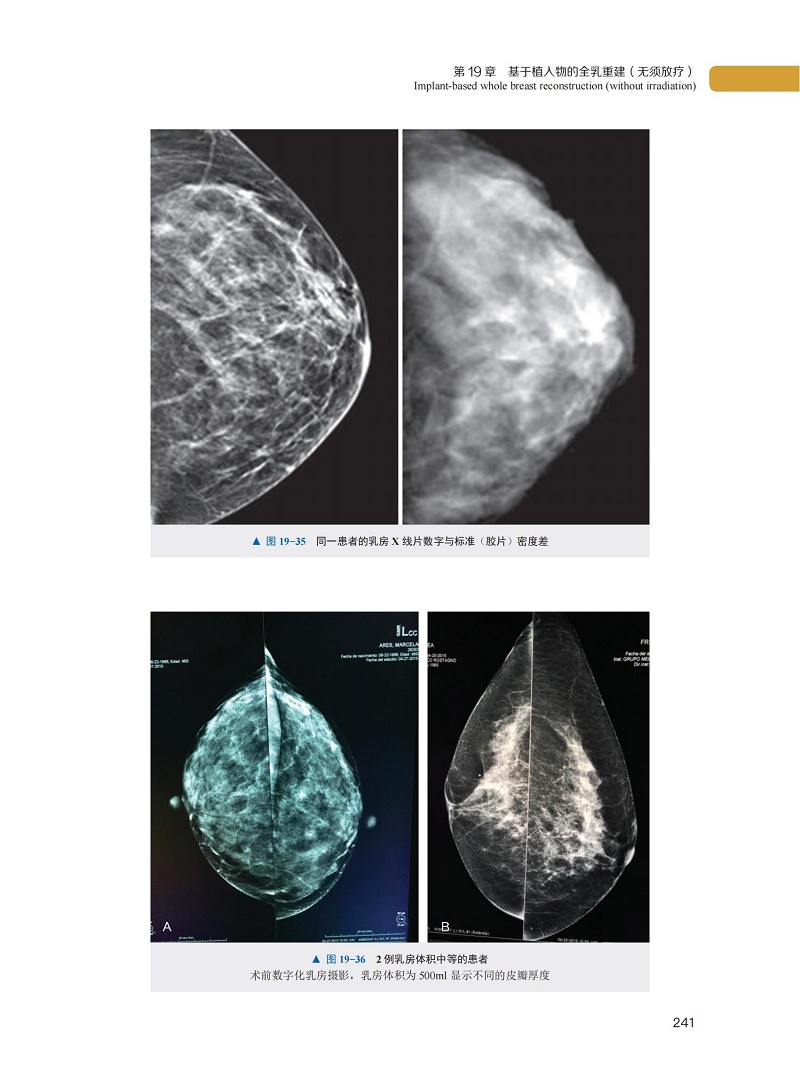

二、全數位化乳房 X 光攝影與數位乳房斷層融合攝影技術的作用

第 19 章 基於植入物的全乳重建(無須放療)